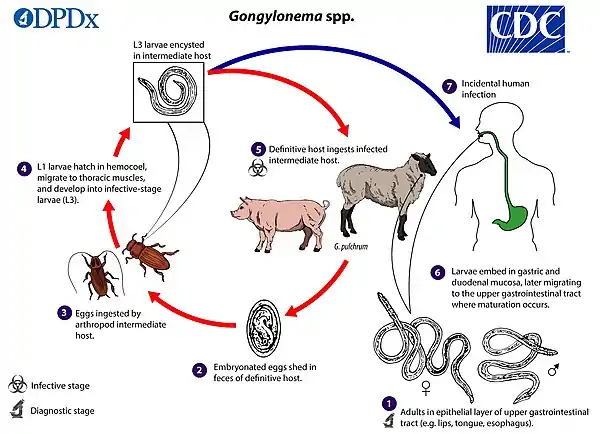

Life cycle

In humans, the hypothesized life cycle is as follows: Ingestion of contaminated food, water, or infected dung beetle. Infects upper esophagus, moves around and lays eggs in buccal cavity of human host, ingested eggs locate near esophagus, develop and mature into adult worms after two subsequent molting stages, migrate into buccal cavity, no eggs are ever found in human feces, which strengthens the assumption that humans are solely incidental, accidental, and dead end hosts for the Gongylonema pulchrum parasite life cycle.

The G. pulchrum parasite has also been studied in vivo in rabbits. The life cycle is as follows:

Infective third stage larva from naturally infected dung beetles (intermediate hosts and vectors), were orally given to rabbits. The larvae entered the upper gastrointestinal tract of the rabbits (esophagus and upper stomach), and then migrated upward into the buccal cavity- pharyngeal mucosa and tongue. A third molt took place 11 days after primary infection, and the final molt took place at 36 days after primary infection. Worms reached sexual maturity at about 8 weeks, and were found mostly in the esophagus of the rabbit. 72–81 days post primary infection, embryonated eggs appeared in the feces of the rabbits.